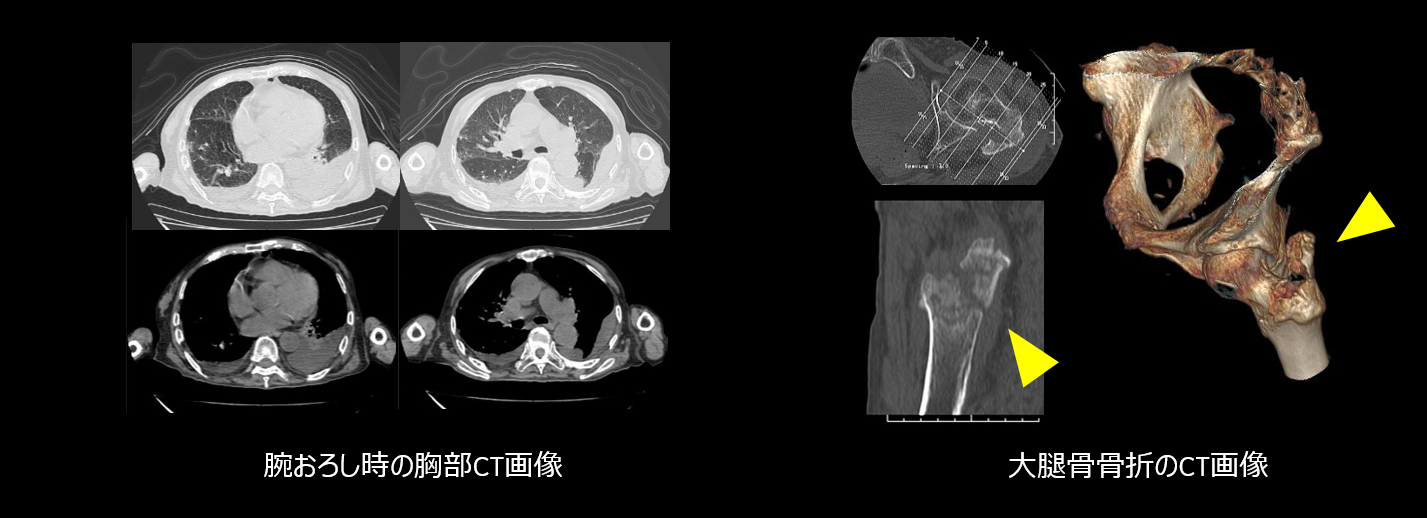

1.16列のディテクターと高速ヘリカルスキャンにより短時間撮影が可能になり、胸部から骨盤までの広範囲撮影も10数秒で終了します。また、従来はルーチン10㎜厚で撮影し、場合によって5mm厚、HRCTの時は1.25㎜で追加撮影していましたが、16列ディテクターの恩恵で、常に1.25㎜厚のデータが使用できるので、追加撮影がなくなりました。

アキシャル断面だけでなく、いわゆるMPR画像(サジタル・コロナル断面)や 3D画質が向上している。

さらに、画像処理の機能も飛躍的に向上しています。16列CTでは、常に1.25mm厚データを収集しているので、MPRや3D画像の需要増加に常に対応可能となりました。撮影プロトコルが比較的自由にカスタマイズ可能でリコン条件は最高10個まで組むことができますし、MPR自動処理を事前に登録しておくことも可能なため、画像処理の時間が大幅に短縮されました。また、Host PCの演算処理スピードが上がっているため、3D作成時の追加・削除機能の処理が早く、全体的に作成しやすくなりました。